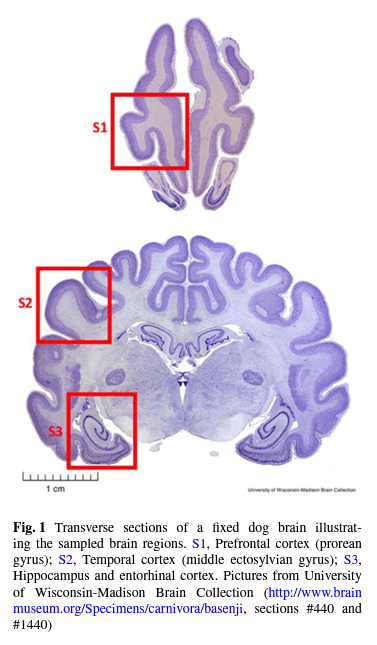

As part of our efforts to understand healthy aging, we explore age-related diseases in dogs and in humans. We have recently found associations between physiological hallmarks of alzheimer’s disease in dog brains and their cognitive performance, opening the door to future investigation and interventional studies of neruodegenerative disease models in companion animals. Urfer, S.R. et al., GeroScience 43, 2379–2386 (2021). https://doi.org/10.1007/s11357-021-00422-1